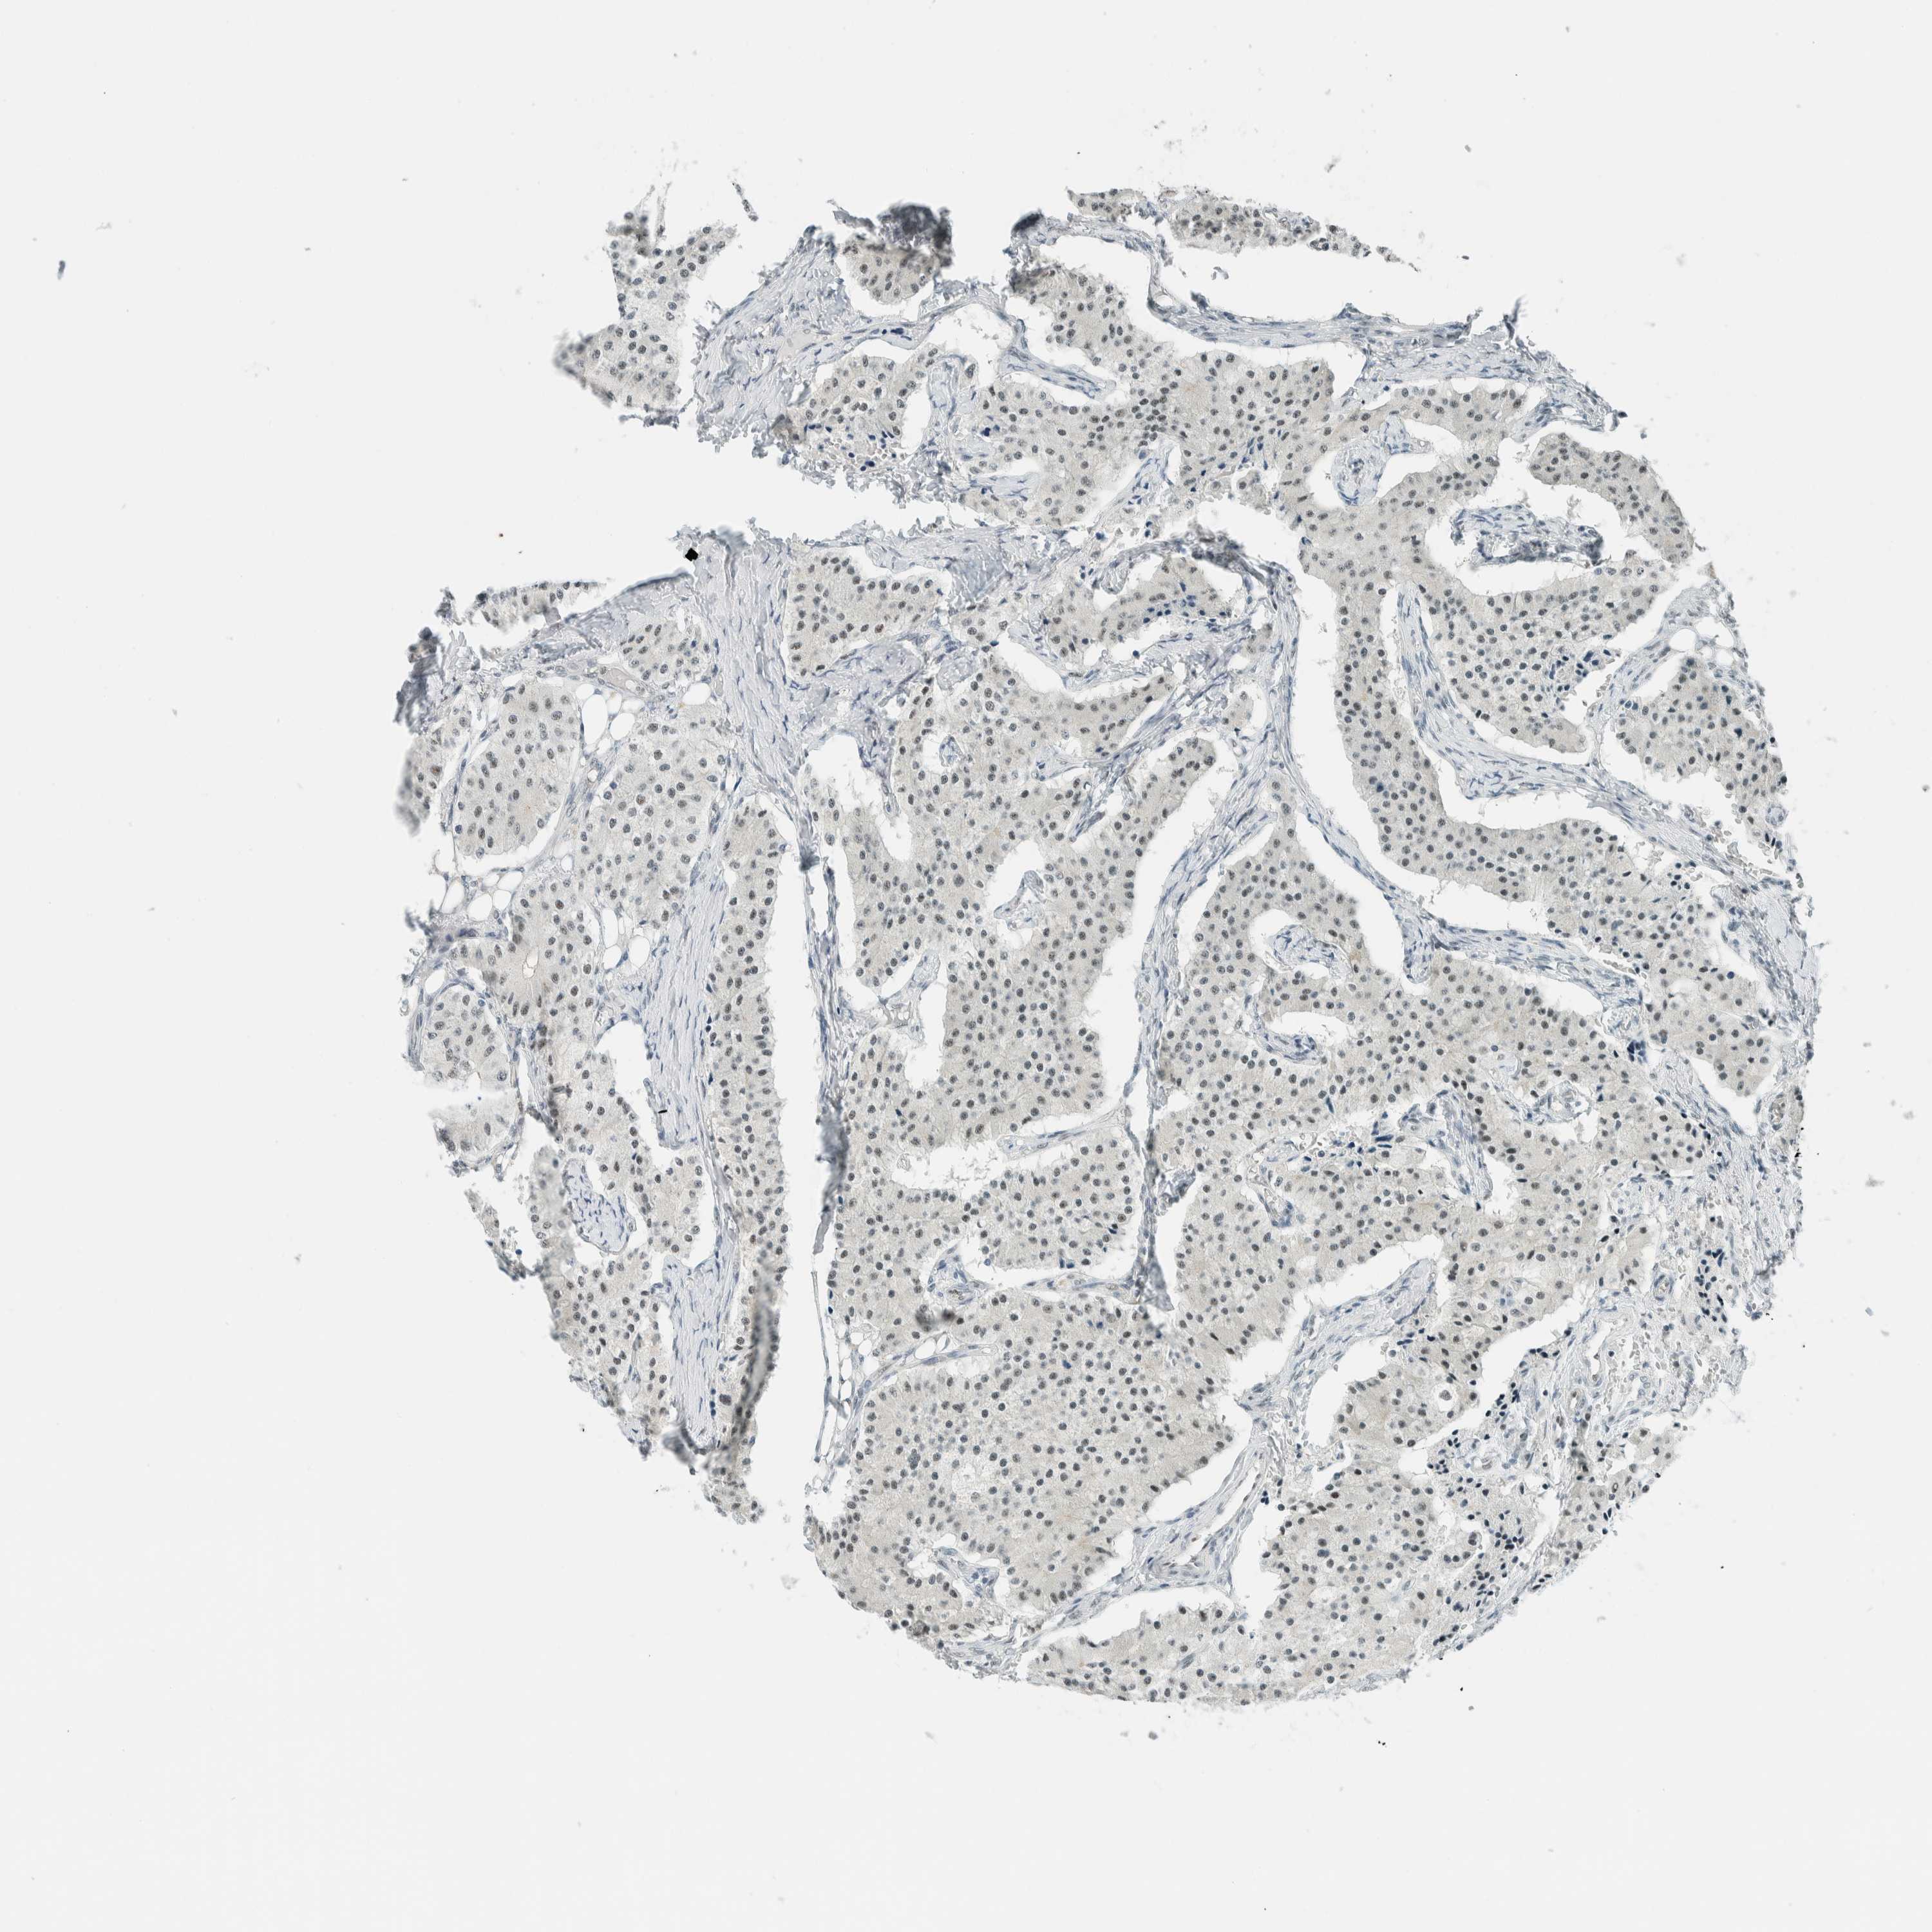

CARCINOID - Protein expressioni

A mouse-over function shows sample information and annotation data. Click on an image to view it in a full screen mode. Samples can be filtered based on level of antibody staining by selecting one or several of the following categories: high, medium, low and not detected. The assay and annotation is described here.

Each image is clickable and will lead to virtual microscopy that enables deeper exploration of all samples and also displays staining intensity scores, fraction scores and subcellular localization as well as patient and tissue information for each sample.

Antibody HPA021883

Antibody HPA021886

Staining

High

Medium

Low

Not detected

Intensity

Strong

Moderate

Weak

Negative

Quantity

>75%

75%-25%

<25%

None

Location

Nuclear

Cytoplasmic/membranous

Cytoplasmic/membranous,nuclear

Carcinoid, malignant, NOS

Carcinoma, NOS